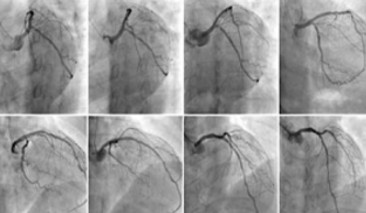

科室目前共有人員20余人,其中醫(yī)生10人,護(hù)理人員10余人,醫(yī)生正高職稱3人,中級(jí)職稱2人,初級(jí)職稱5人??剖叶ㄆ谘?qǐng)國(guó)內(nèi)知名專家授課,并派科內(nèi)中青年業(yè)務(wù)骨干輪流到國(guó)內(nèi)著名醫(yī)院進(jìn)修學(xué)習(xí),定期參加國(guó)內(nèi)重要的心血管學(xué)術(shù)會(huì)議??剖曳e極與國(guó)際全新診療技術(shù)接軌,在濰城區(qū)率先開(kāi)展了冠狀動(dòng)脈造影、PCI、起搏器植入術(shù)等技術(shù),成功搶救了大量急性心肌梗死、病竇綜合征、三度房室傳導(dǎo)阻滯、心臟驟停等急危重癥患者。

冠心病介入診療中心

心血管內(nèi)科在心血管首席專家、學(xué)科帶頭人韓海英主任醫(yī)師的帶領(lǐng)下,秉著“生命所系、健康所托”的宗旨,傳承著“時(shí)間就是心肌,心肌就是生命”的白衣天使的誓言,一直致力于挽救患者生命及提高患者生活質(zhì)量,建立急性胸痛處理的綠色通道,成功挽救了成千上萬(wàn)患者的生命,為挽救壞死心肌做出了最大的努力。醫(yī)院特聘原濰坊市人民醫(yī)院急診科張言鎮(zhèn)主任為心內(nèi)科首席專家,大力開(kāi)展冠狀動(dòng)脈介入治療,為挽救更多心肌梗死病人提供最快、最優(yōu)、最佳的治療方案。